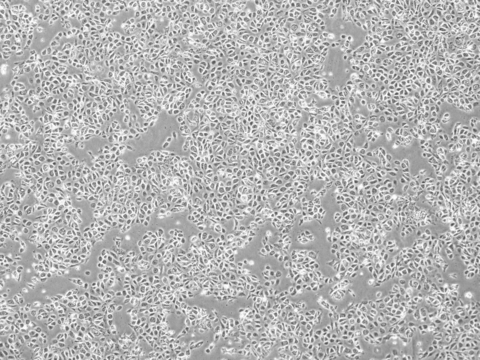

Photo caption: Karis Bio iPSC-Derived Endothelial Cells. Photo credit: Karis Bio

The collaboration is set to accelerate the development of Karis Bio’s innovative autologous iPSC-derived endothelial cell (iPSC-EC) therapy designed to generate new blood vessels in ischemic organs. Karis Bio’s first-in-human clinical study in South Korea leverages patient-specific iPSCs to restore blood flow and repair damaged tissues, offering patients a revolutionary alternative to conventional invasive procedures such as stents or bypass surgery, while eliminating the risk of immune rejection.